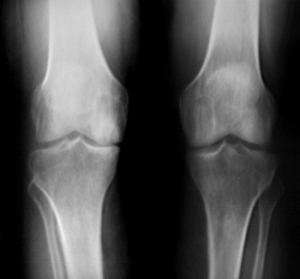

X-rays can help in the diagnosis and may be the only special test required in the majority of cases. X-rays can also help doctors rule out other problems, since knee pain from OA may be confused with other common causes of knee pain, such as a torn meniscus or kneecap problems. In some cases of early OA, X-rays may not show the expected changes.